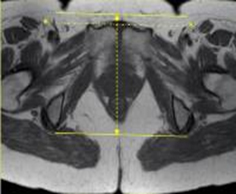

SAG T2 SPAIR TSE 3-4 mm 0.5-1mm SPAIR 20cm Ischial tuberosity to ischial tuberosity (NOT skin to skin)

MRI Pelvis Sports Hernia WO MSK Protocol image 3